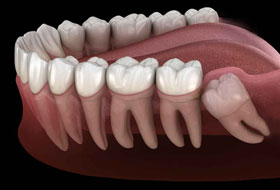

Wisdom teeth generally erupt into the mouth by the age of 18 years and may even extend upto 22 years or even later. They may erupt into the oral cavity depending on the space available or may remain in the bone unerupted. Their eruption into the oral cavity depends on many factors like the space available, the position of the tooth, early shedding of the other teeth.

The gum overlying the tooth may get infected causing severe pain and discomfort radiating to the jaws, ear, temple region. The wisdom teeth, if they erupt in an abnormal position cause changes in the temporomandibular joint leading to problems over a period of time and also can damage to the adjacent teeth. The abnormal position of the teeth may cause difficulty in brushing and maintaining good hygiene of the teeth.